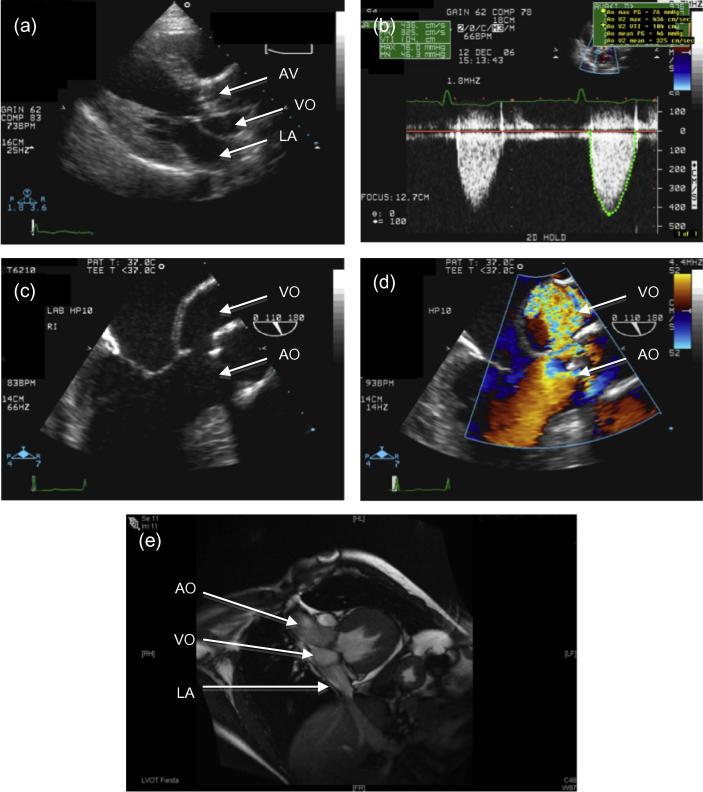

The use of modern cardiac imaging techniques suggests that congenital ventricular diverticulum (CVD) may be more common than generally believed and may present asymptomatically in adult life. We present a case of congenital left ventricular diverticulum diagnosed in a patient presenting with myocardial infarction (MI). The case highlights the importance of the differential diagnosis of CVD from post infarct left ventricular aneurysms (PILVA) and suggests that adult studies using modern imaging techniques are needed to define the prognosis for asymptomatic CVD in order to guide management.

现代心脏成像技术的应用表明,先天性心室憩室(CVD)可能比普遍认为的更为常见,并且可能在成年期无症状出现。我们报告一例在表现为心肌梗死(MI)的患者中诊断出的先天性左心室憩室病例。该病例突出了将CVD与心肌梗死后左心室室壁瘤(PILVA)进行鉴别诊断的重要性,并表明需要开展使用现代成像技术的成人研究来确定无症状CVD的预后,以指导治疗。